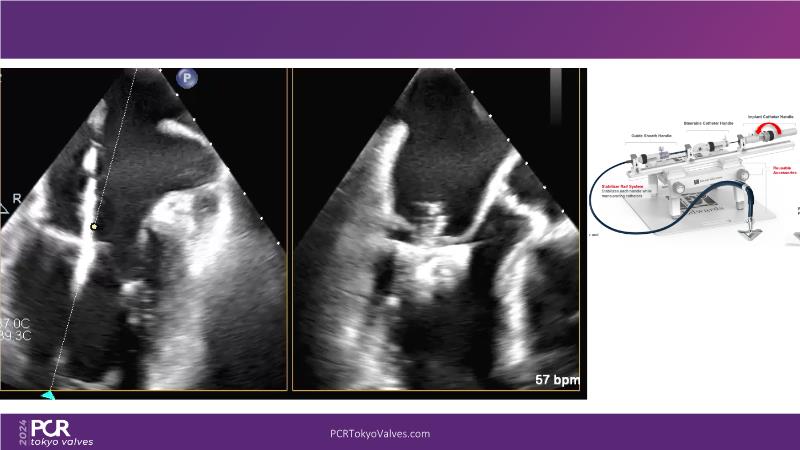

Watch this session to get an overview of a new TEER device, follow the step-by-step procedure related to initial experiences with this device for a Japanese patient with degenerative mitral regurgitation, learn about the latest data from RCT and registries, and follow discussions of challenging TEER cases!

- To understand how novel TEER device provides new possibilities in TEER

- To learn procedural step-by-step of novel device